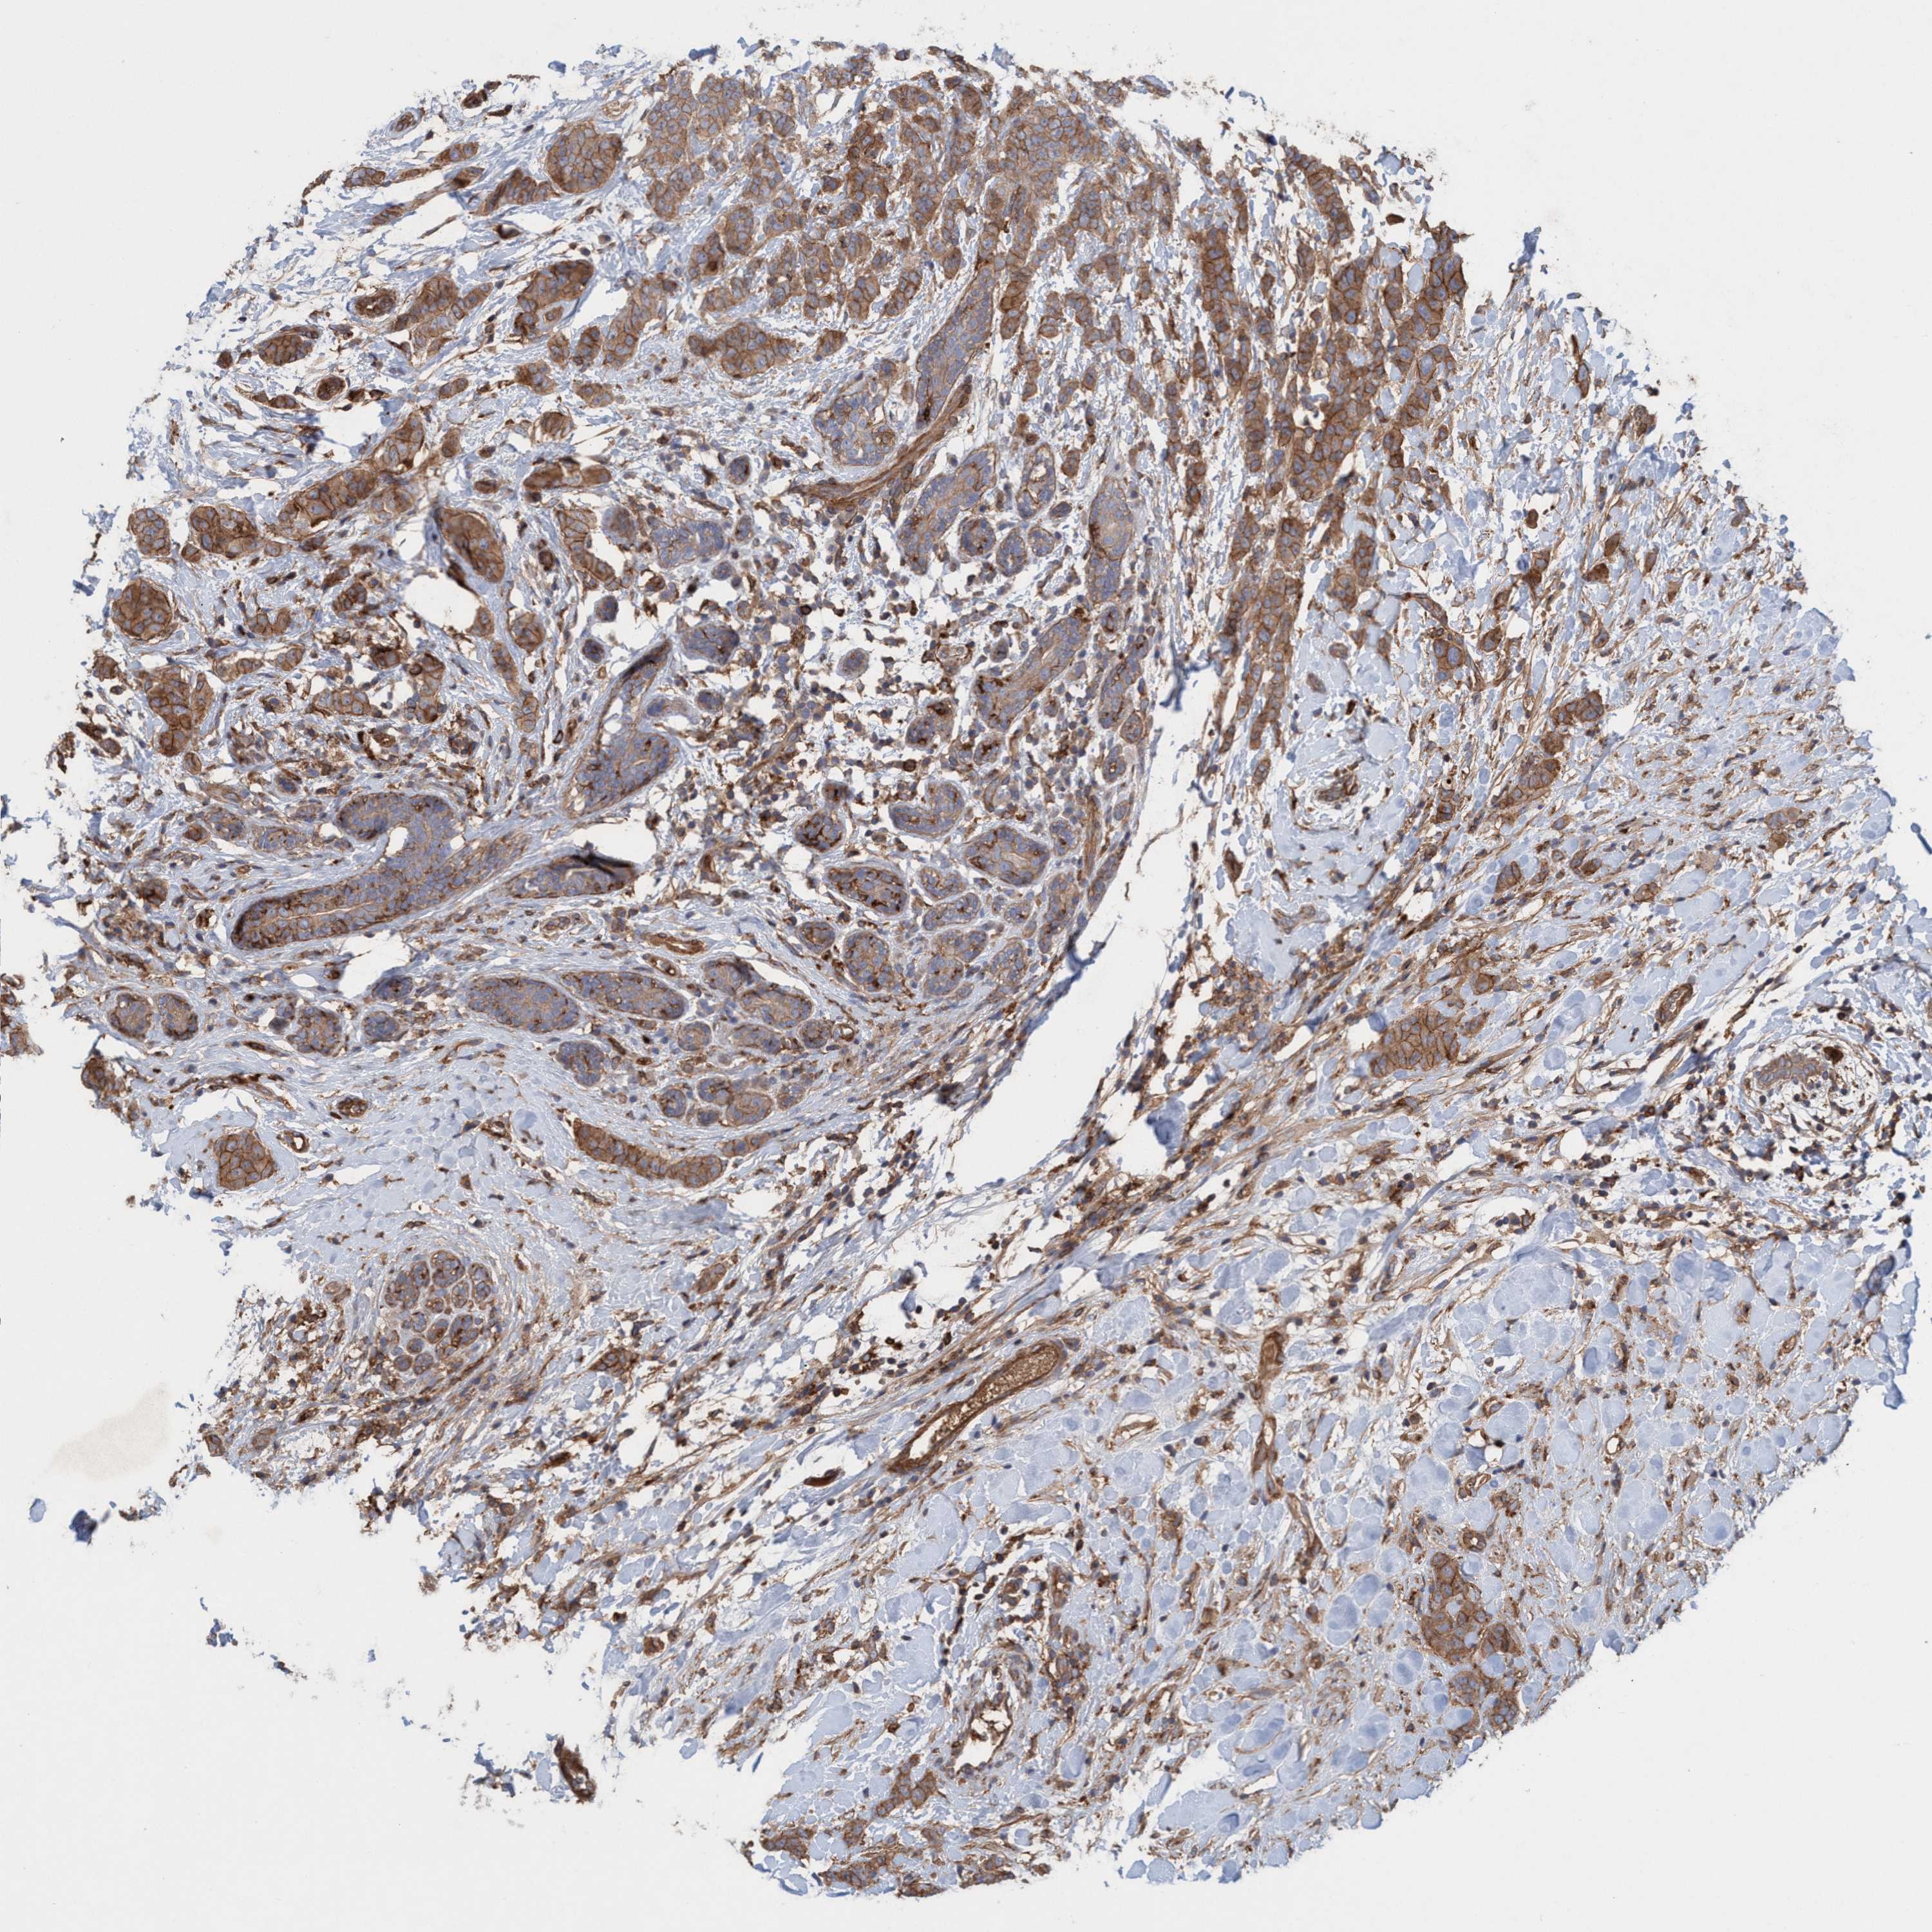

BRCA TCGA BRCA VALIDATION PROTEIN EXPRESSION

ANTIBODIES

AND

VALIDATION